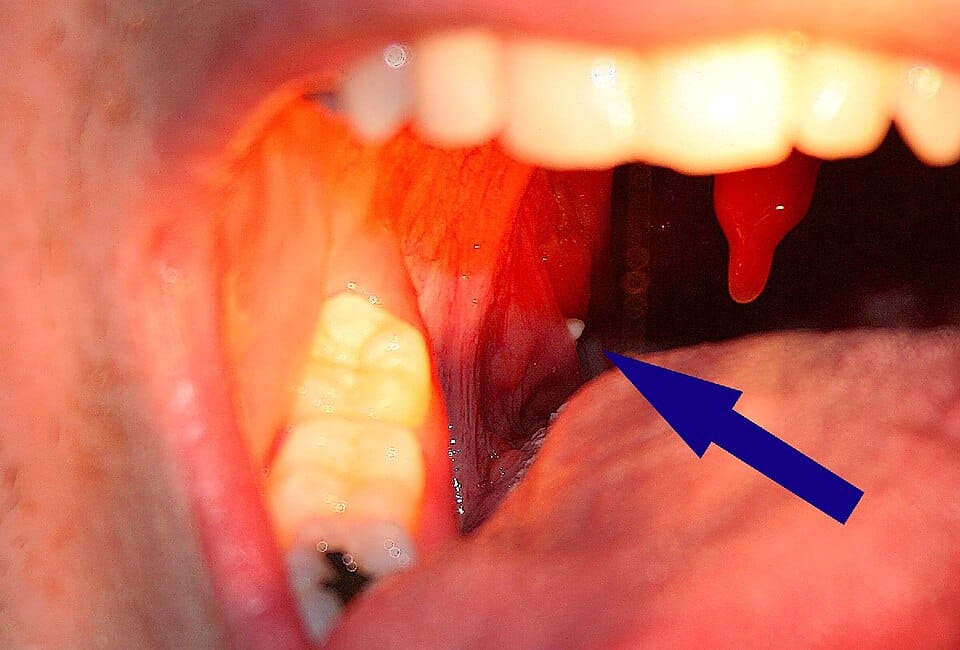

Gros plan sur des calculs amygdaliens

Contrairement aux apparences, ces petites masses ne sont pas des cailloux mais des amalgames de débris organiques. Nos amygdales, avec leurs cavités naturelles (les cryptes), piègent divers éléments : particules alimentaires, cellules desquamées, bactéries. Au fil du temps, ce mélange se solidifie, prenant cette teinte caractéristique entre le blanc cassé et le jaune pâle.